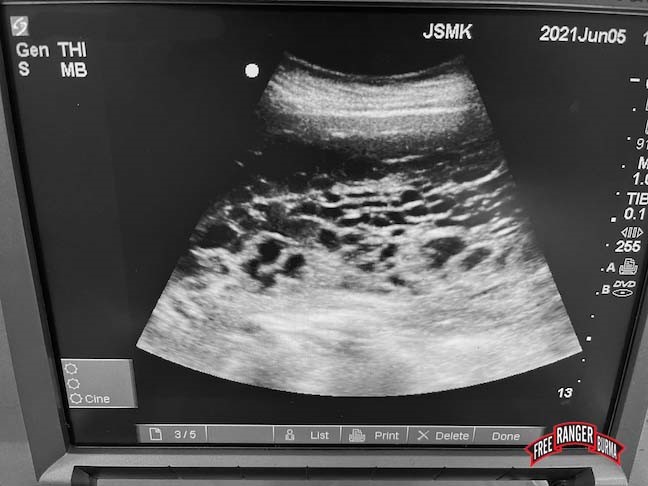

This year FBR’s Jungle School of Medicine-Kawthoolei (JSMK) introduced a life-saving procedure for mothers experiencing a particularly dangerous problem: a molar pregnancy. The procedure is the first step in the treatment of molar pregnancies, which are a sort of false pregnancy in which the womb is filled with inert tissue that can become cancerous if not removed. While molar pregnancies are uncommon elsewhere, women from South-East Asia are more prone to suffer from them. In 2021 alone, JSMK saw four women with molar pregnancies. They arrived from surrounding villages in the mountains of Karen State, accompanied by family members, and complaining of bleeding and pain.

The molar pregnancy procedure, called Dilation and Curettage (D&C) was introduced this year during the monsoon season by Dr John Shaw, JSMK’s international medical director. He normally practices in the United States, but traveled to JSMK three times this year to teach in the local medic training program, supervise the clinic, and perform minor surgeries. He performed the D&C procedure while teaching it to Toh Win, JSMK’s medical director, as well as to Dr. Remeline Damasco, another American visiting physician at JSMK. Dr. Damasco then performed the procedure on one patient, and Toh has done it four times thus far, treating one molar pregnancy, and three incomplete miscarriages. The necessary equipment was graciously donated in 2020.

Thanks to the introduction of D&C for initial treatment of molar pregnancy, the lives of four young mothers were saved at JSMK. The women were then referred to another clinic in Karen State for subsequent testing and additional treatment to prevent any progression of the disease to cancer. By performing the D&C and arranging treatment and follow-up with our partner clinic, JSMK was able to manage molar pregnancy locally. In the past, the condition was managed by referral to a neighboring country, but that option is not currently available due to the Covid pandemic and the coup in Myanmar. In addition, as the entire treatment may require two months of care, this localized care permits women to remain closer to home and family.